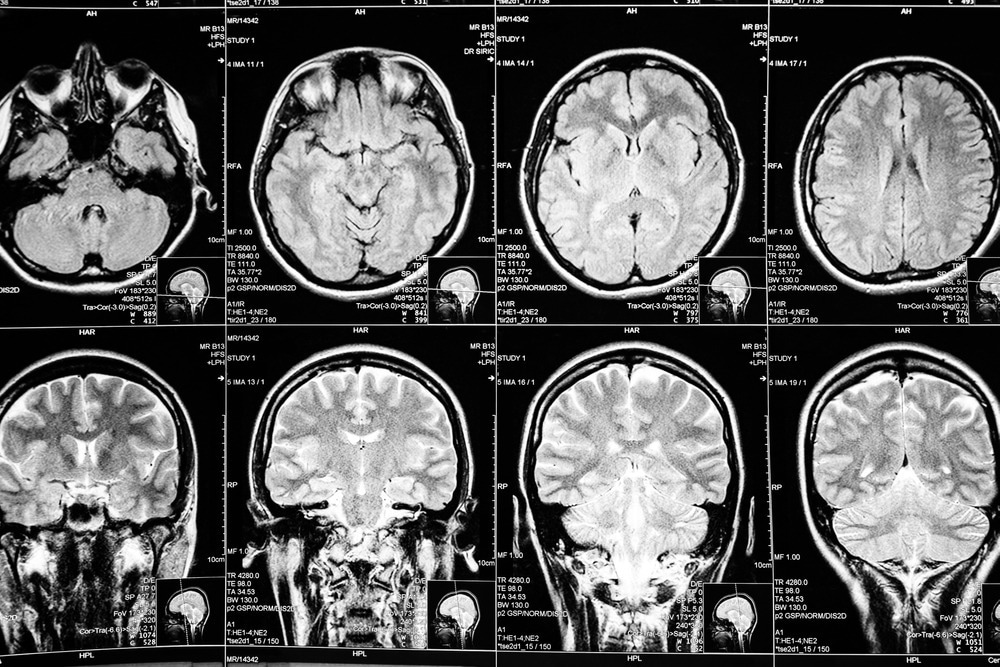

Study: Altered brain regional homogeneity is associated with depressive symptoms in COVID-19. Image Credit: Stivog / Shutterstock.com

Recent advances in neuroimaging literature have allowed researchers to study COVID-19-related structural brain alterations. Magnetic resonance imaging (MRI), for example, has highlighted abnormalities in the medio-temporal lobe, as well as the detection of white matter microhemorrhages, in COVID-19 patients.

MRI scans were obtained within nine months of the positive SARS-CoV-2 test, followed by image processing.  Regional homogeneity (ReHo) analysis was carried out to determine local brain abnormalities when the brain is at rest.